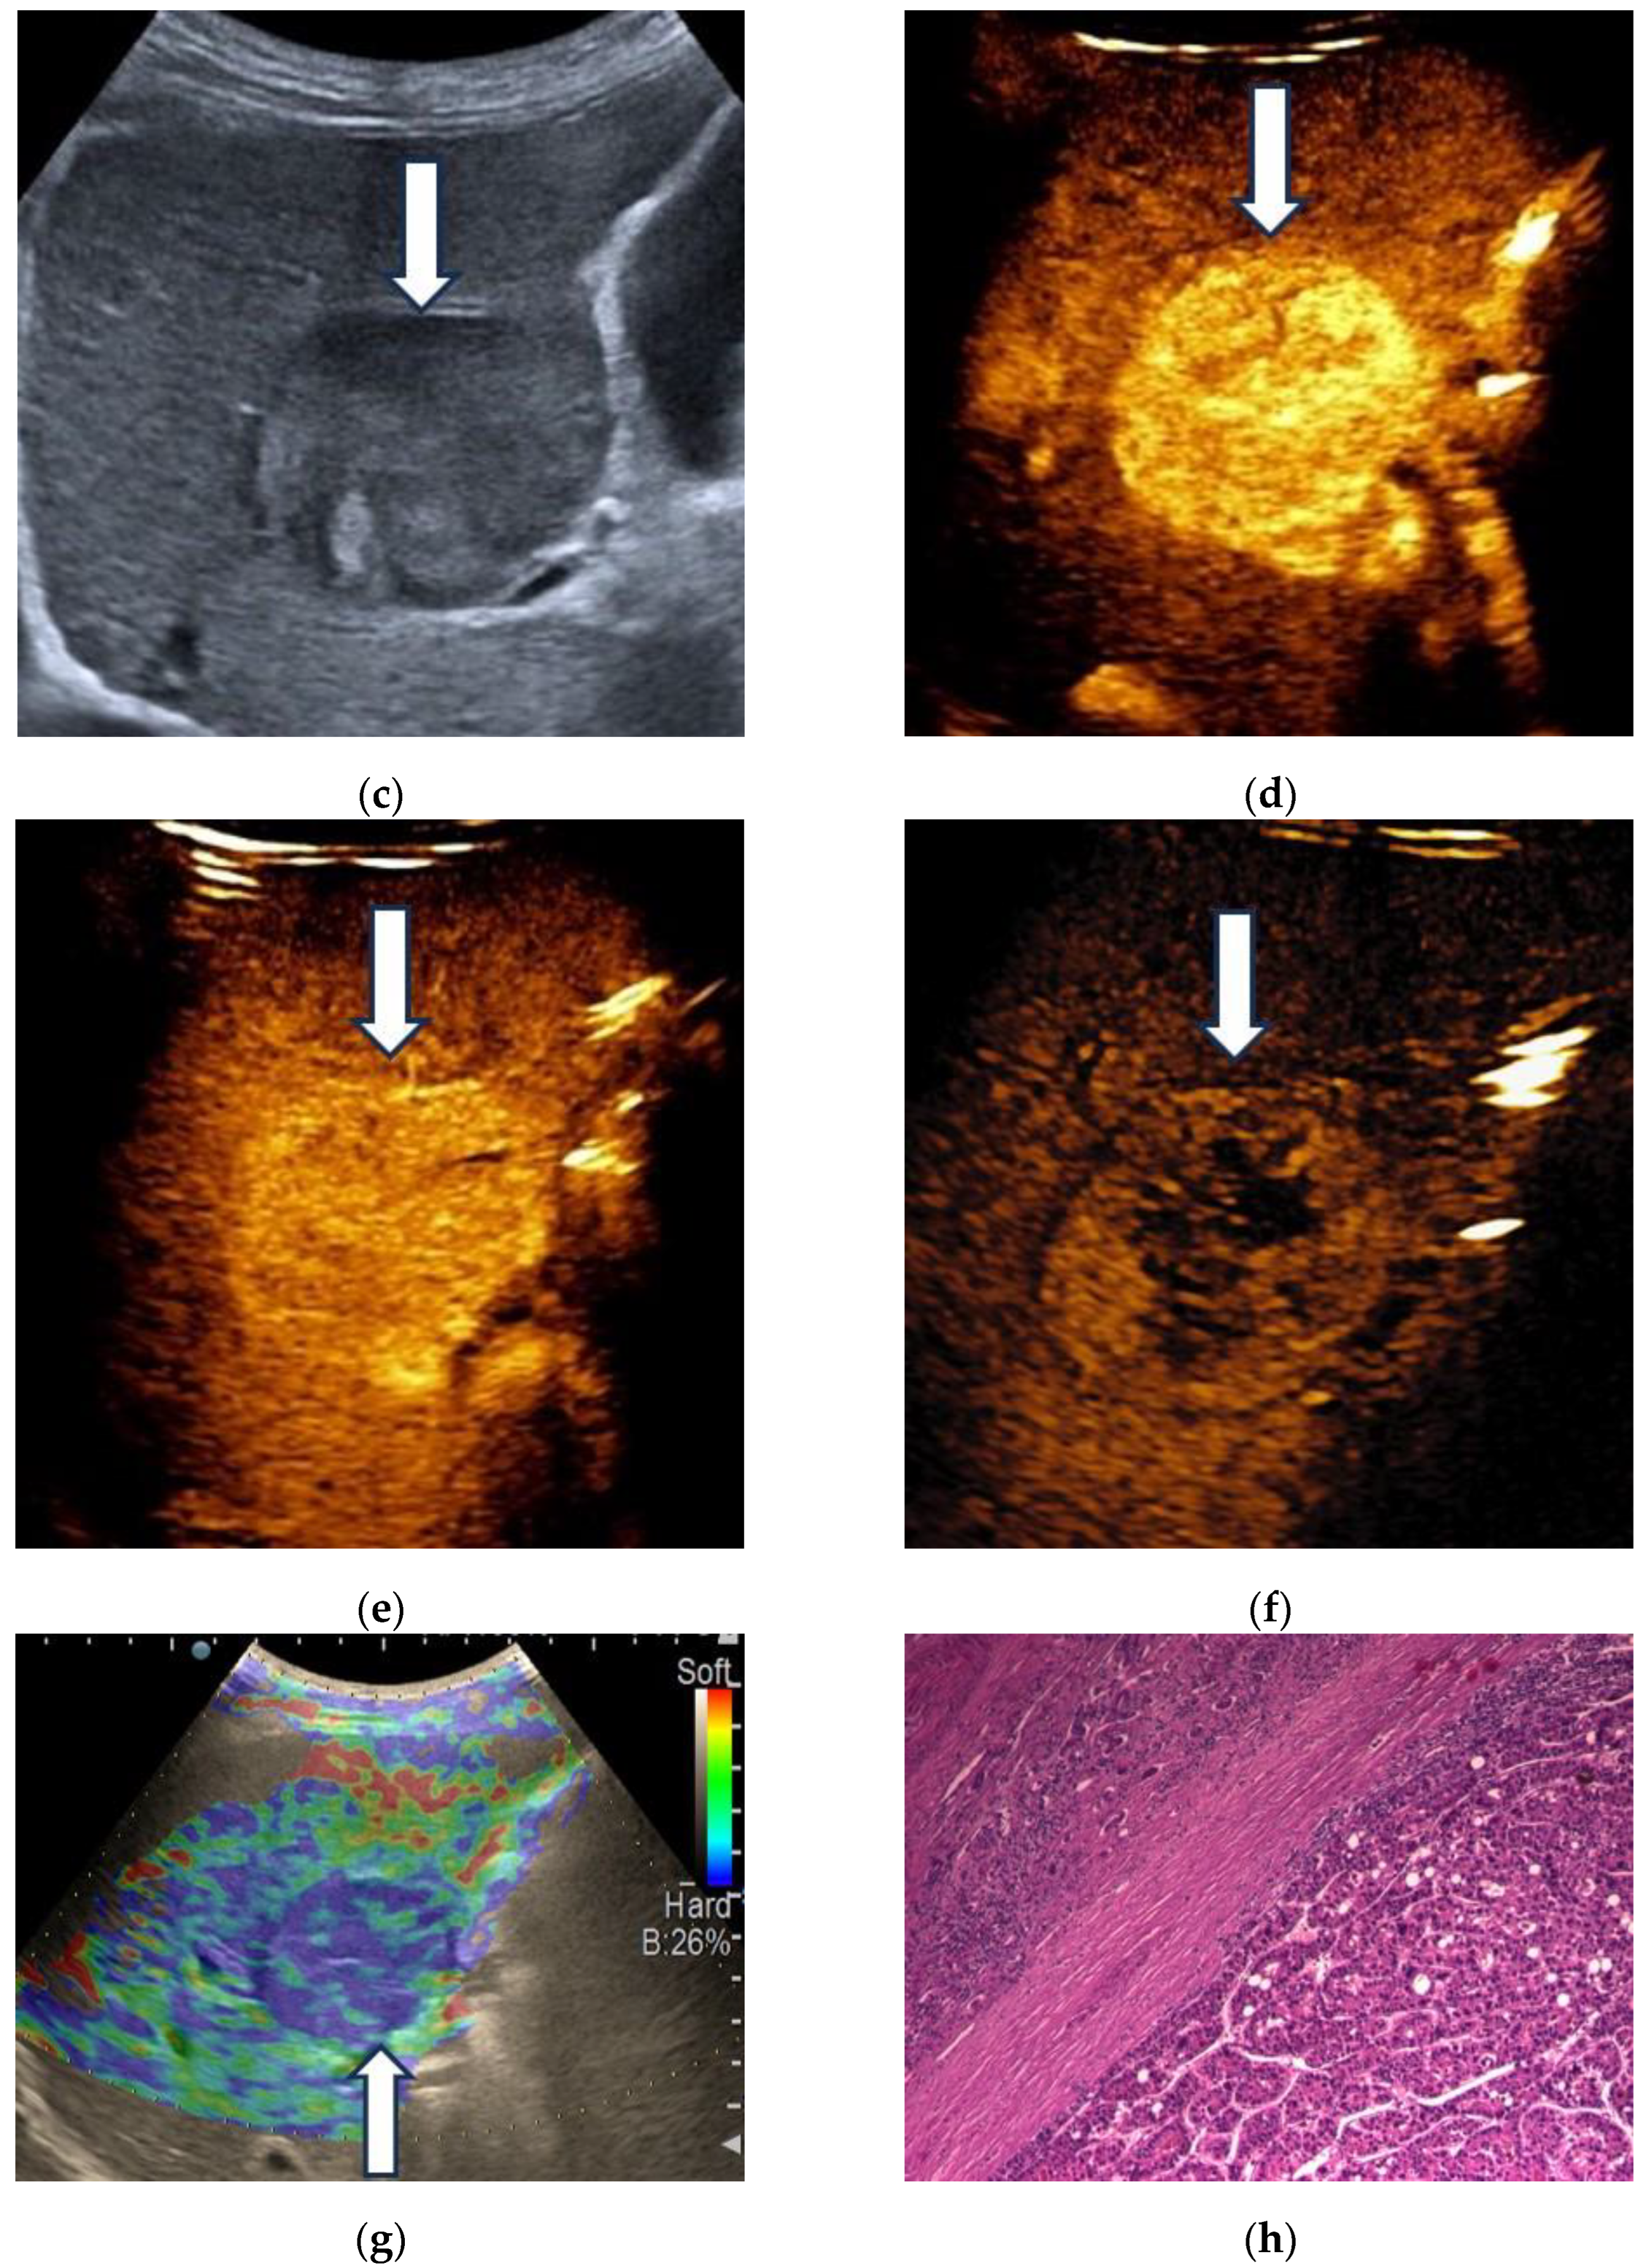

3.1. B-Mode Ultrasound

3.2. Contrast-Enhanced Ultrasound

3.3. Shear Wave Measurements in Liver Tumors

3.4. Real-Time Tissue Elastography